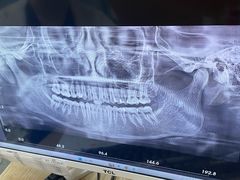

• 同步齿科·数字化正畸种植口腔中心(珠海店)

• -同步齿科·数字化正畸种植口腔中心(珠海店)